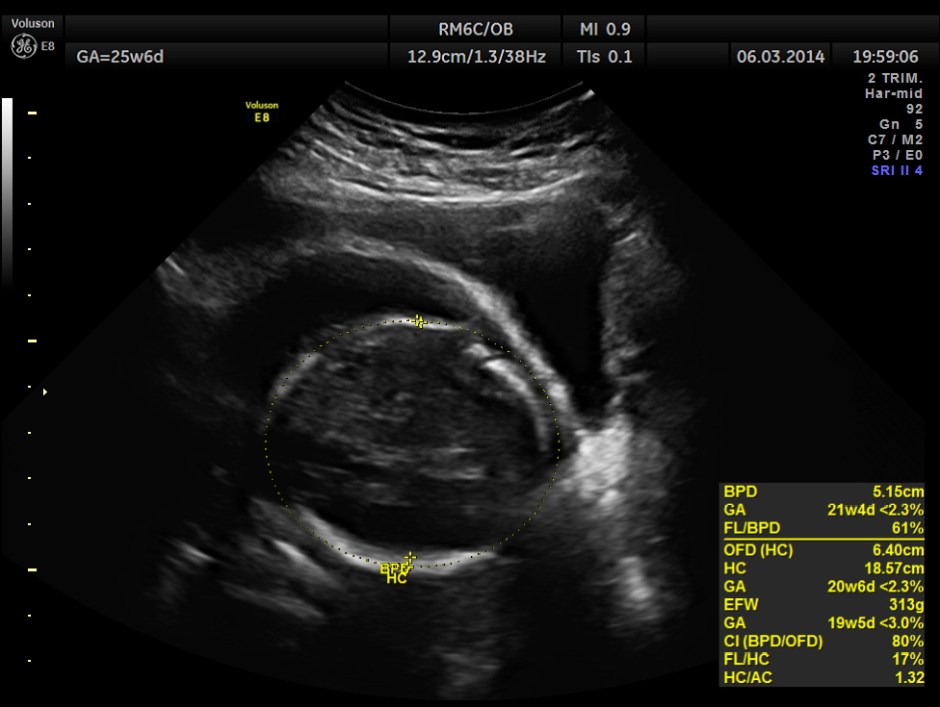

The GA was around 25 weeks , but the AUA was around 19 to 20 weeks. All parameters – BPD, HC, AC, FL are < 2.3 %tile and all other long bones are < 5.0 %tile.